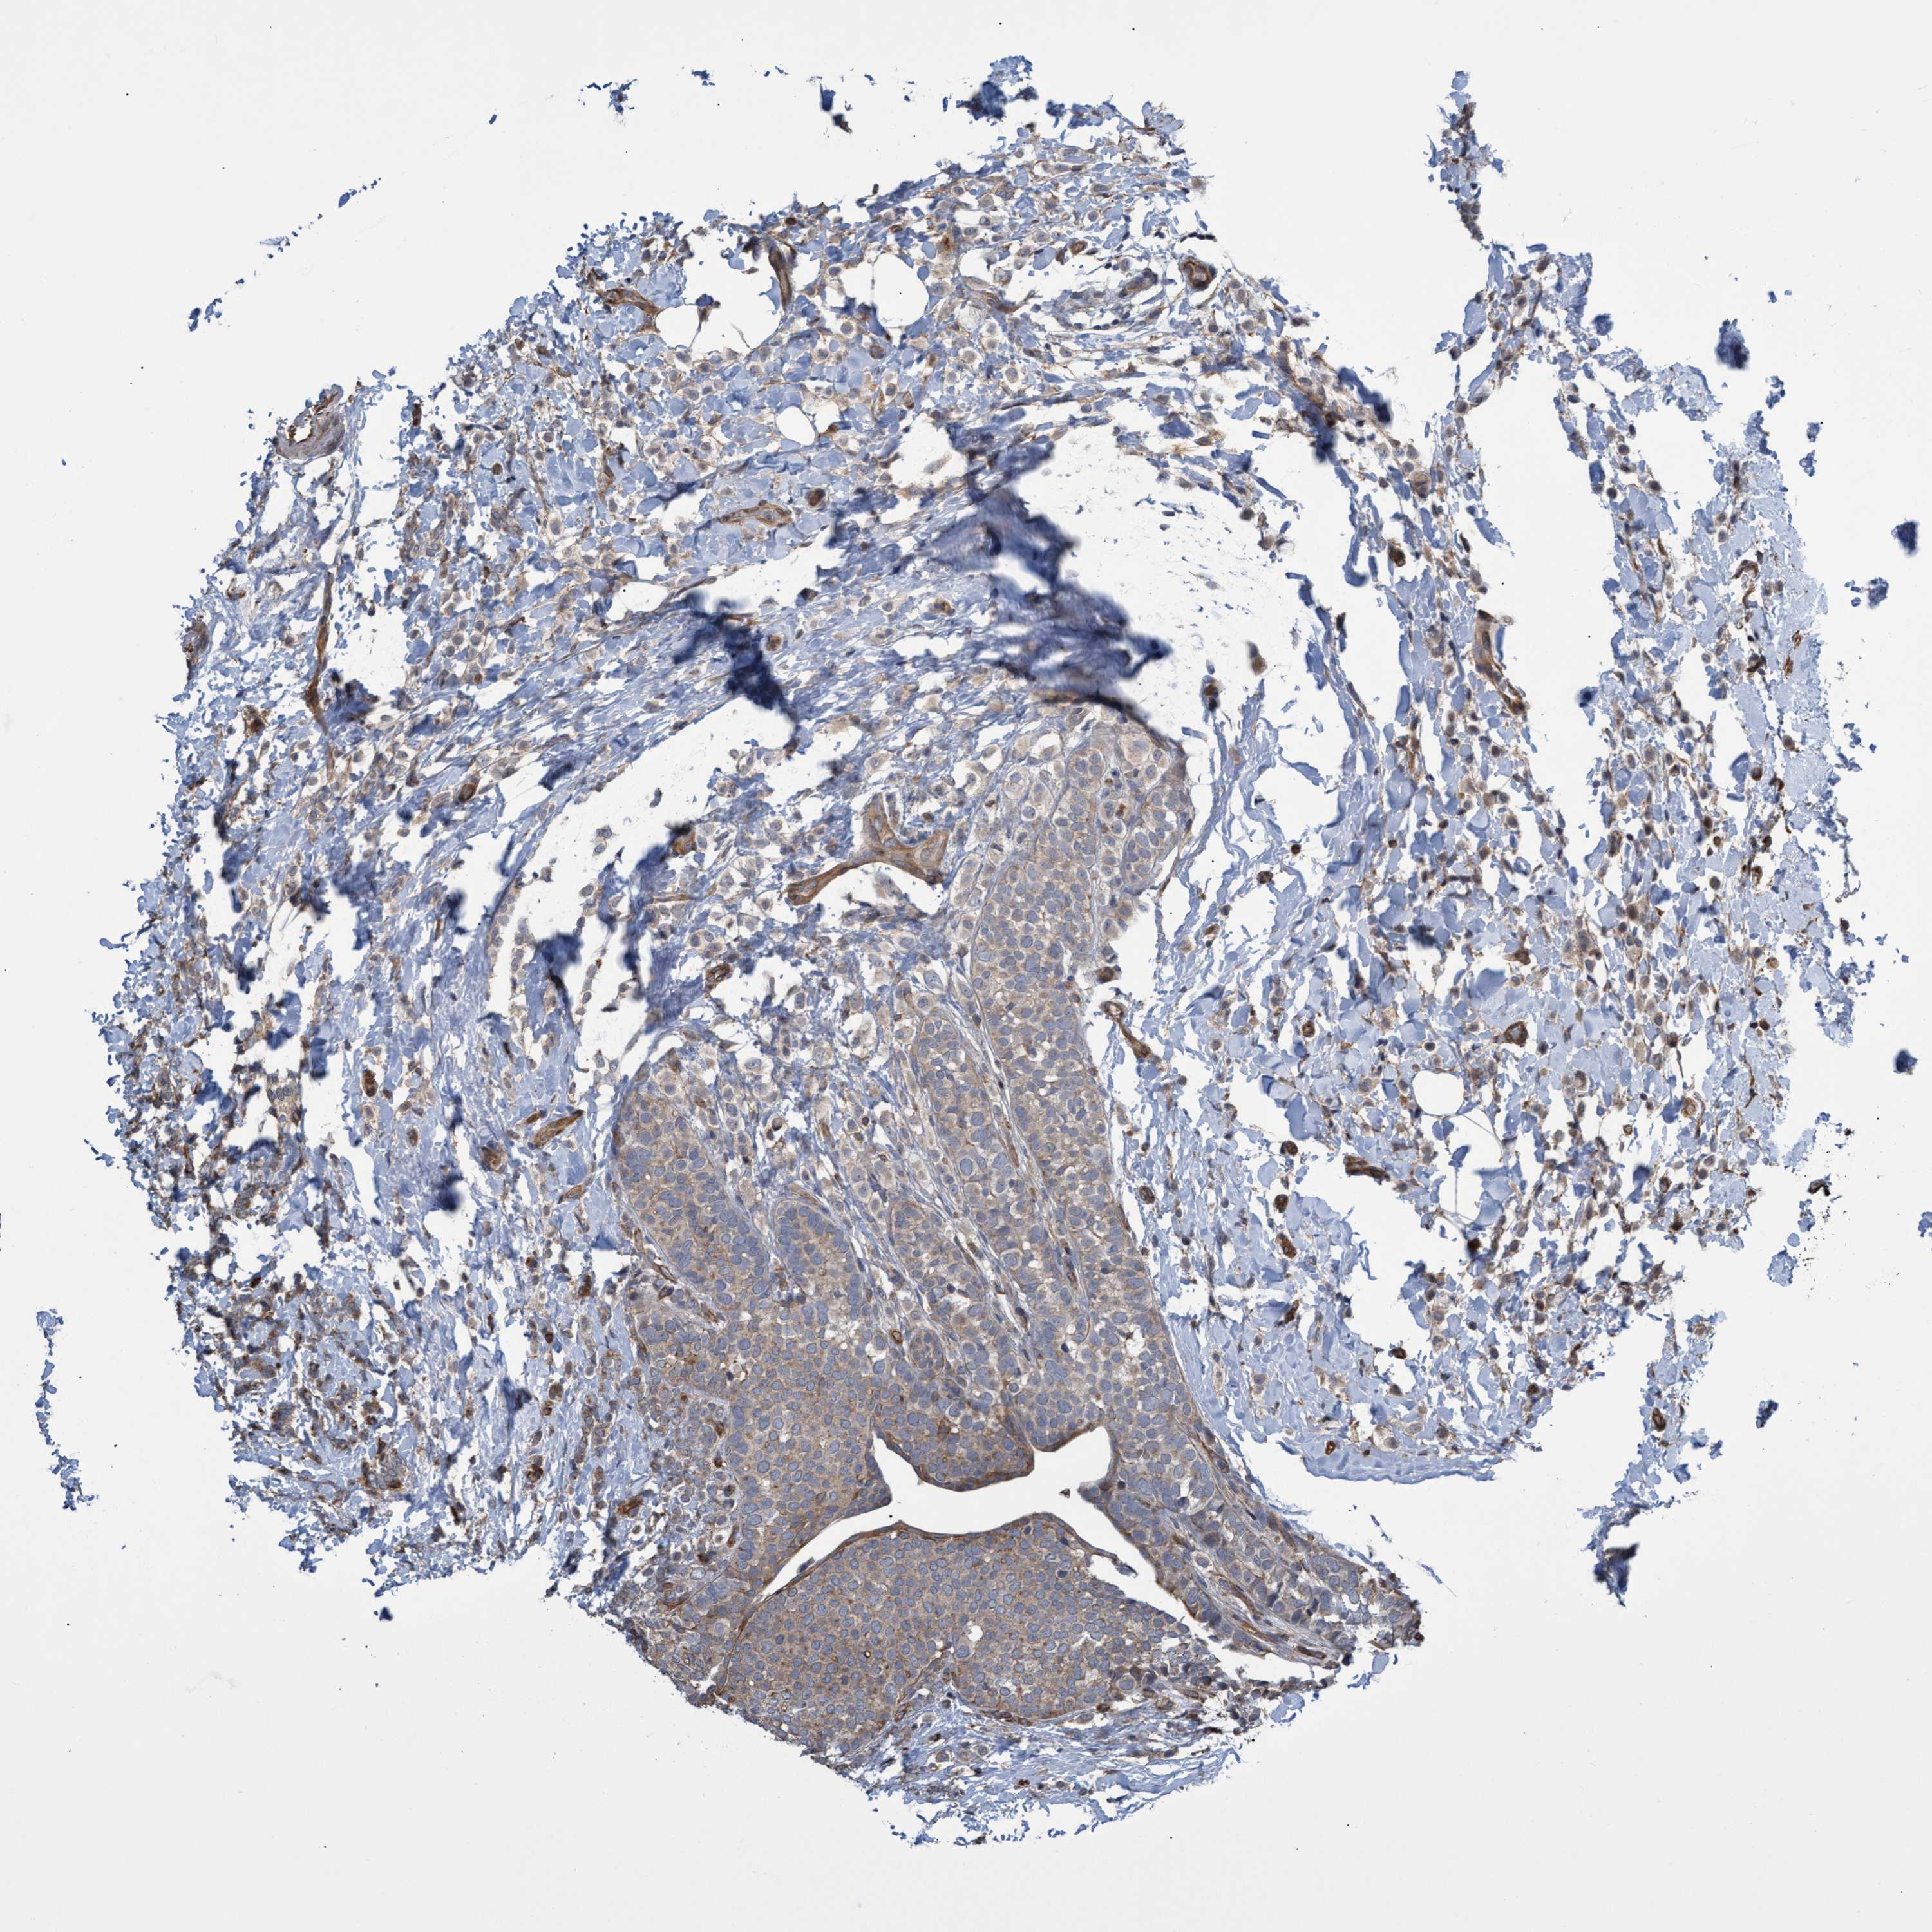

BRCA TCGA BRCA VALIDATION PROTEIN EXPRESSION